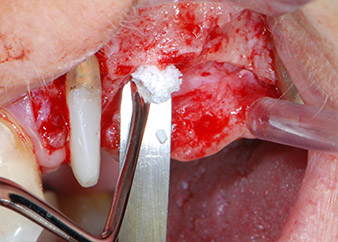

Prior to implant placement, infected tissue was removed from the alveolar bone in the implant site and around the abutment teeth with an insert originally designed for bone shaping and collecting bone chips (Piezomed, insert B5) (Figs. 6 and 7).

Implant beds were prepared at sites 25 and 26 with rotary instruments, used in a contra-angle handpiece with a 20 : 1 transmission ratio with an updated powerful implant motor (Implantmed, W&H) (Fig. 8).